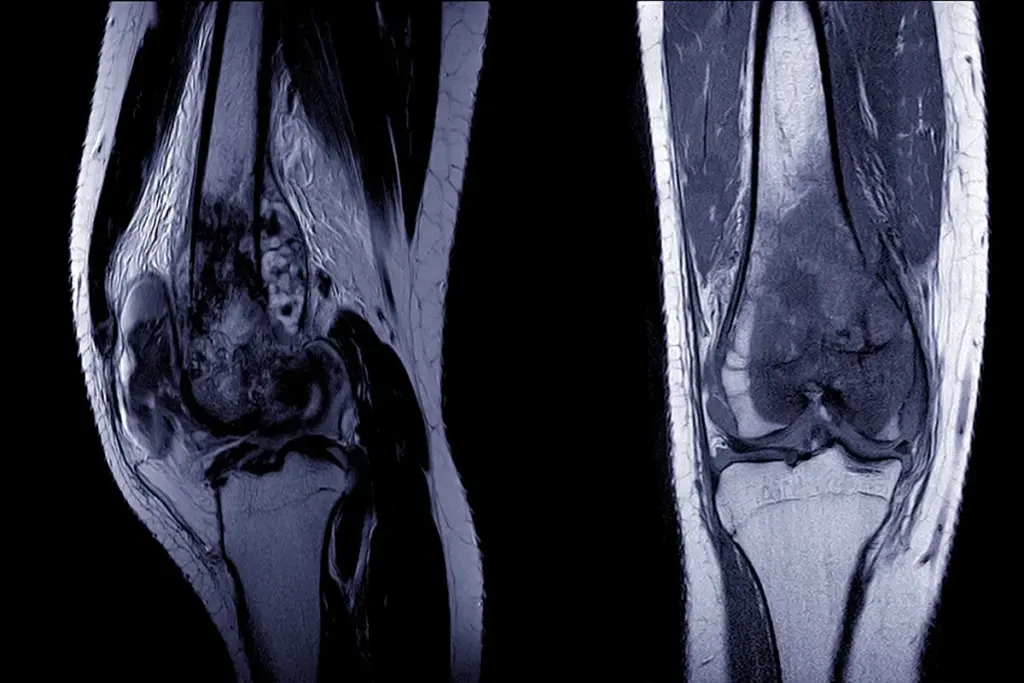

1. Imaging: MRI is the preferred modality for soft‑tissue assessment, while CT scans provide detailed bone evaluation. PET‑CT can detect metastatic spread.

3. Pathology: Immunohistochemistry and molecular testing (e.g., FISH, RT‑PCR) identify specific translocations or mutations.

Staging follows the American Joint Committee on Cancer (AJCC) TNM system, which considers tumor size (T), nodal involvement (N), and distant metastasis (M). Precise staging guides treatment planning and prognostication.